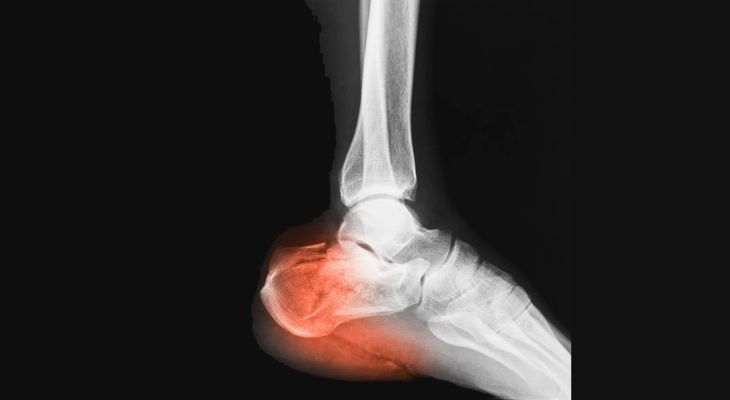

Patní ostruha a plantární fascitida

Patní ostruha

K nejčastějším příznakům ostruhy patní kosti patří bodavá bolestivost v patní krajině, která se objevuje při nášlapu a mnohdy i při pouhém doteku paty a je lokalizována vprostřed paty, může vystřelovat do plosky. Dále se může objevit zarudnutí paty, otok a později i různé nárůstky v oblasti úponu Achillovy šlachy - "Haglundova pata"